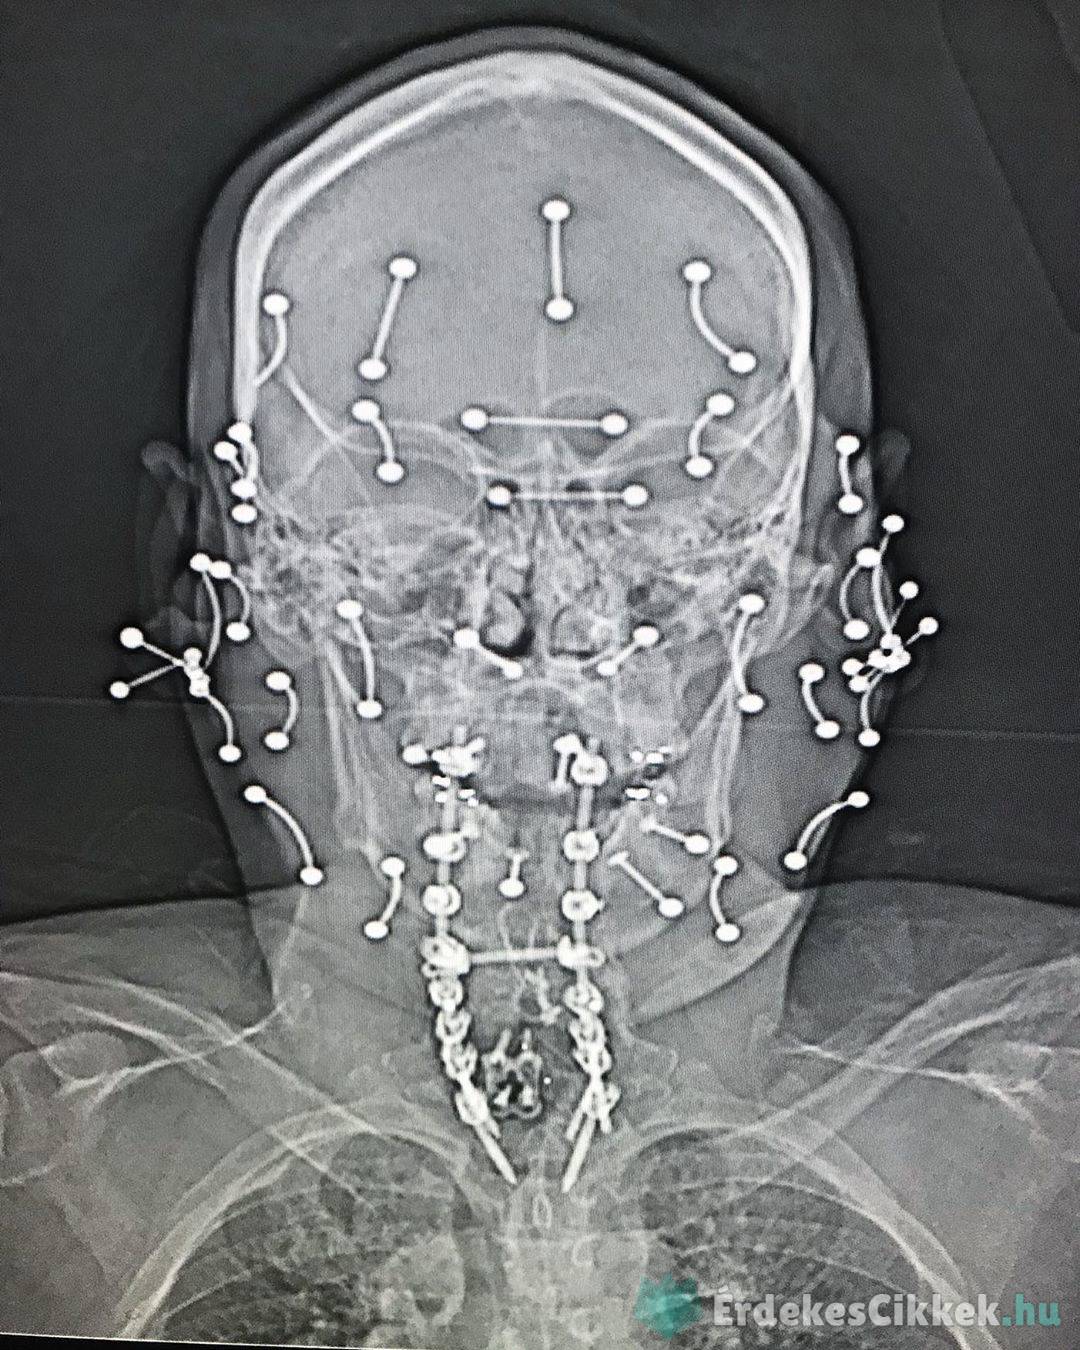

3, Így nlz ki egy piercinggel rendelkező férfi röntgenfelvétele.